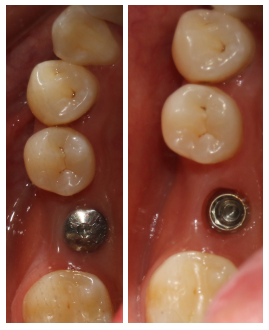

2017年5月31日 46消毒,拆线。

2017年9月30日 46二期+取模。

2017年10月24日46戴牙